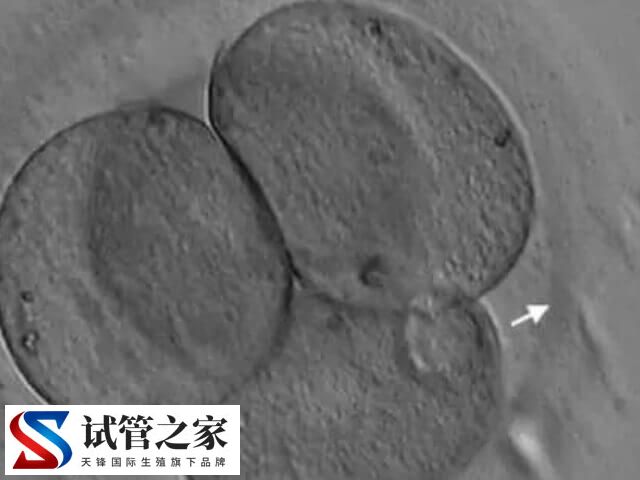

胚胎发育到囊胚阶段时,需突破透明带才能着床。若透明带过厚、过硬或形态异常,可能阻碍胚胎自然孵化。辅助孵化(人体胚胎孵化项目)相当于为胚胎“开窗”,使其更易与子宫内膜接触,增加着床机会。至于这适合哪些人,如下所示:

也就是说,通过化学、机械、或激光的方法对透明带进行打薄、打孔甚至完整切除,以帮助胚胎从透明带内孵化出来的技术,而这就是辅助孵化技术,旨在提高辅助生殖的成功率。